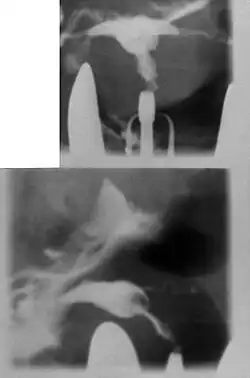

A T-shaped uterus with circular constriction noted around the proximal portion of the marker. The lower uterus appears tapered and narrow.

Women are often diagnosed with this condition after several failed pregnancies, proceeded by exploratory diagnostic procedures, such as magnetic resonance, sonography, and particularly hysterosalpingography.[6][7][8] In such studies, a widening of the interstitial and isthmus of uterine tube is observed, as well as constrictions or narrowing of the uterus as a whole, especially the lower and lateral portions, hence the "t" denomination. The uterus might be simultaneously reduced in volume, and other abnormalities might be concomitantly present.[9]